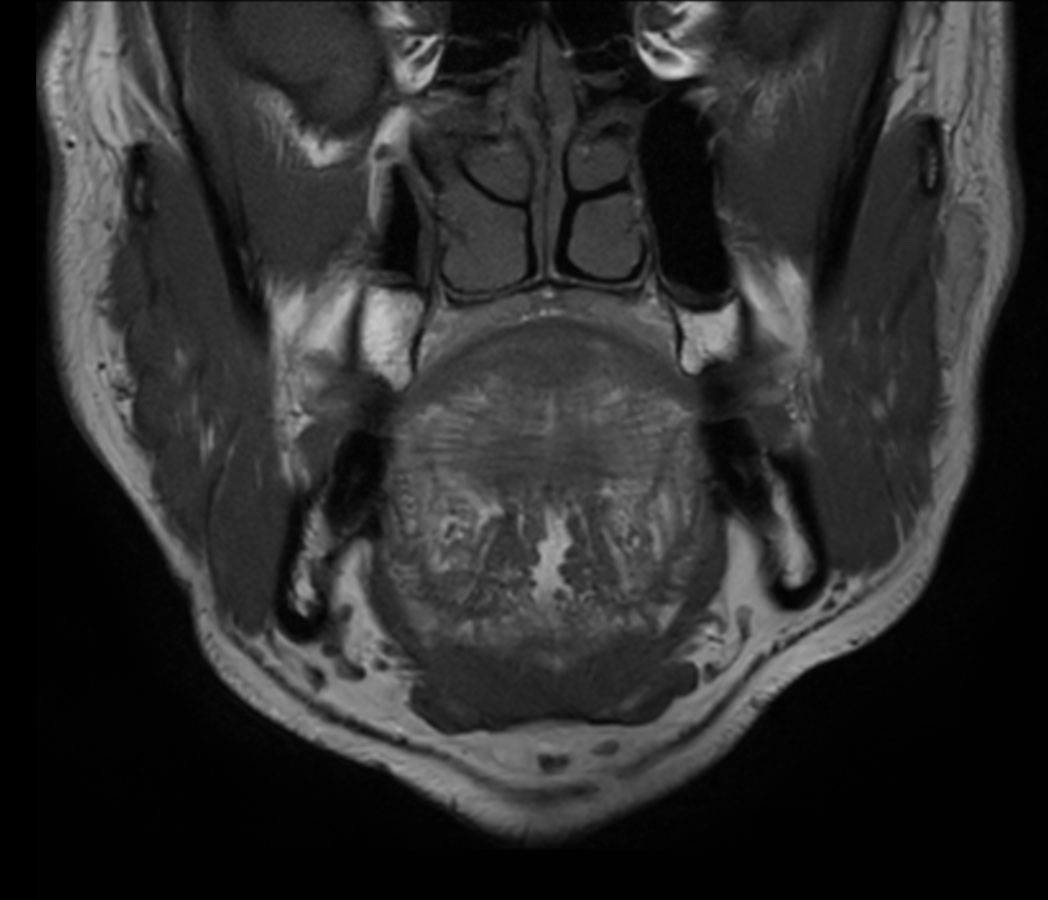

Coronal T1w TSE